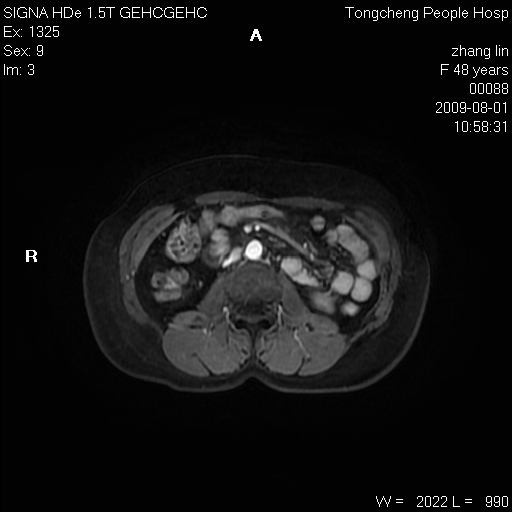

女,48岁。健康体检,彩超发现右肾占位性病变。平素健康。

临床诊断:右肾占位性病变,性质待定(囊肿?肿瘤?)。

上中腹部mr平扫+增强扫描,图像如下:

右肾上极见一类圆形病灶,t1wi呈等信号t2wi呈等高混杂信号,三期增强无强化,边界清---考虑囊肿出血。

同反相位均表现为等信号,病变无强化,考虑含蛋白的囊肿可能,弥散加权相或许有些帮助,

慢性胆囊炎